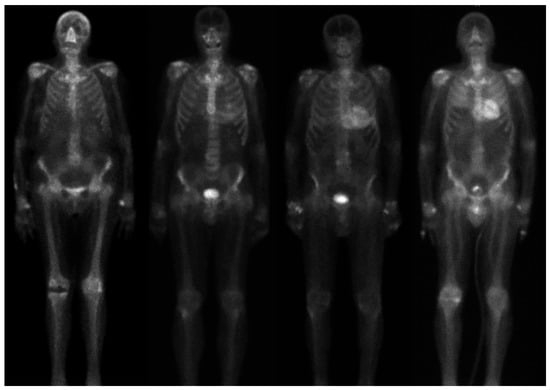

4.5. Senior Athlete with Unexplained Myocardial Hypertrophy and Suspected Cardiac Amyloidosis